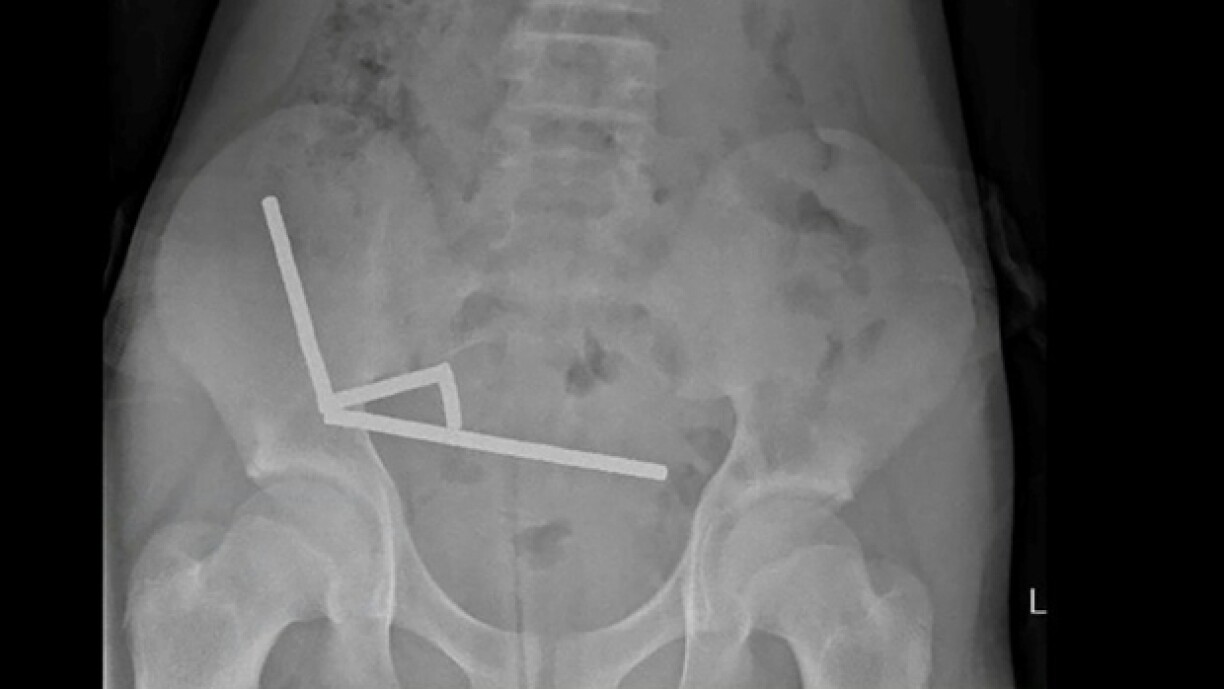

De Jong hat sech no véier Deeg iwwer staarke Bauchwéi beschwéiert a koum an e Spidol op Tauranga. Hei konnten d’Doktere feststellen, dass d’Magnéiter sech am Daarm zesummegezunn haten an esou plazeweis zu Nekrosë (ofgestuewent Geweebe) gefouert hunn.

An enger Operatioun goufen net just d’Magnéiter erausgeholl, ma och dat beschiedegt Geweebe huet mussen erausoperéiert ginn.